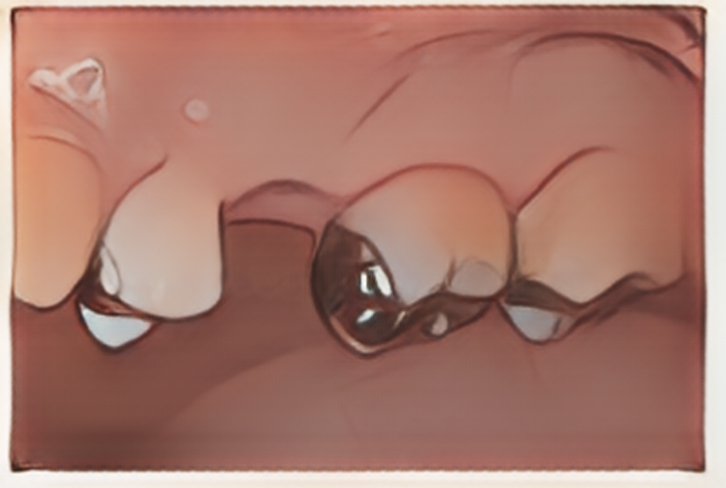

患者様は奥歯を1本失われ、治療方針を含めた相談のために来院されました。歯の欠損部位とその周りの歯の状況を調べていくと、残った歯の部分にも複数の虫歯があることが確認できました。

銀の詰め物を外したところ、広範囲の虫歯のため、かぶせ治療が必要な状況でした。